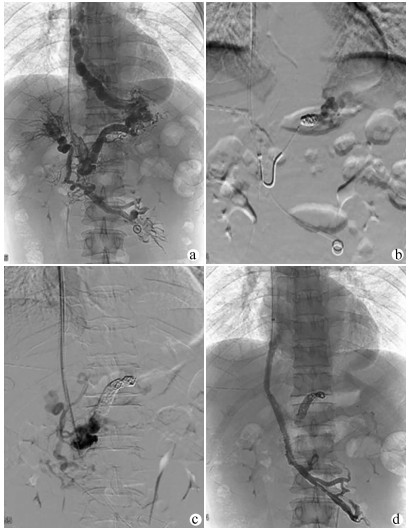

Value of transjugular intrahepatic portosystemic shunt in the prevention of esophageal variceal rebleeding in patients with portal vein thrombosis after splenectomy

•   Objective  To investigate the technical success rate and outcome of transjugular intrahepatic portosystemic shunt (TIPS) in preventing esophageal variceal rebleeding in patients with portal vein thrombosis (PVT) after splenectomy.  Methods  A retrospective analysis was performed for the clinical data of 46 patients with PVT after splenectomy who were admitted to Shandong Provincial Hospital from December 2009 to January 2017 and underwent TIPS to prevent esophageal variceal rebleeding. According to the success or failure of TIPS, the patients were divided into TIPS success group with 38 patients and TIPS failure group with 8 patients. The two groups were compared in terms of postoperative variceal rebleeding, stent dysfunction, hepatic encephalopathy (HE), and survival. The paired t-test was used for comparison of continuous data between two groups, and the chi-square test was used for comparison of categorical data between two groups. The Kaplan-Meier curve was used to analyze variceal rebleeding-free rate, stent patency rate, HE-free rate, and survival rate, and the log-rank test was used for comparison of cumulative rebleeding-free rate and cumulative survival rate.  Results  The technical success rate of TIPS was 82.6%. There were significant differences in 6-, 12-, and 24-month cumulative rebleeding-free rates between the TIPS success group and the TIPS failure group (94.3%/89.8%/89.8% vs 85.7%/85.7%/28.6%, χ2=4.563, P=0.033). In the TIPS success group, the 6-, 12-, and 24-month cumulative stent patency rates were 79.3%, 74.3%, and 69.0%, respectively, and the 6-, 12-, and 24-month cumulative HE-free rates after TIPS were 72.1%, 55.5%, and 55.5%, respectively. There were significant differences in 6-, 12-, and 24-month cumulative survival rates between the TIPS success group and the TIPS failure group (94.0%/94.0%/86.2% vs 71.4%/71.4%/71.4%, χ2=4.988, P=0.026).  Conclusion  TIPS is a safe and feasible method for preventing esophageal variceal rebleeding in patients with PVT after splenectomy, and TIPS combined with a percutaneous transhepatic approach may promote technical success.